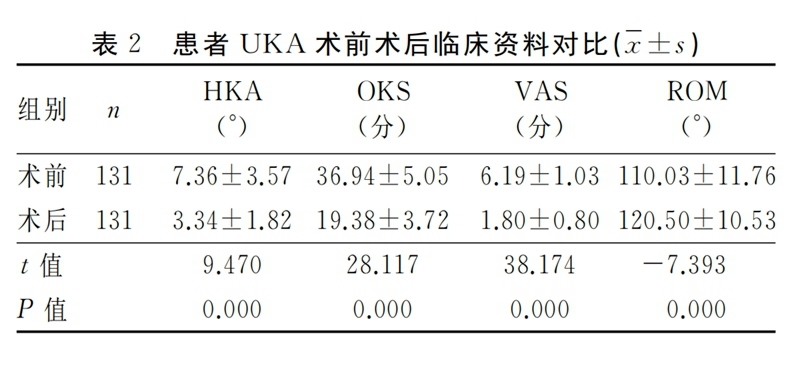

纳入本研究的患者均获得随访,随访时间12~30个月,平均随访时间(19.01±3.80)个月,术前A组、B组、C组三组患者在性别、年龄、BMI及手术侧别等方面无明显统计学差异,见表1。UKA手术前后HKA、OKS评分、VAS评分、ROM情况见表2。UKA术前术后对比,膝关节功能明显改善,差异有统计学意义(P<0.05)。

2.2 组间比较